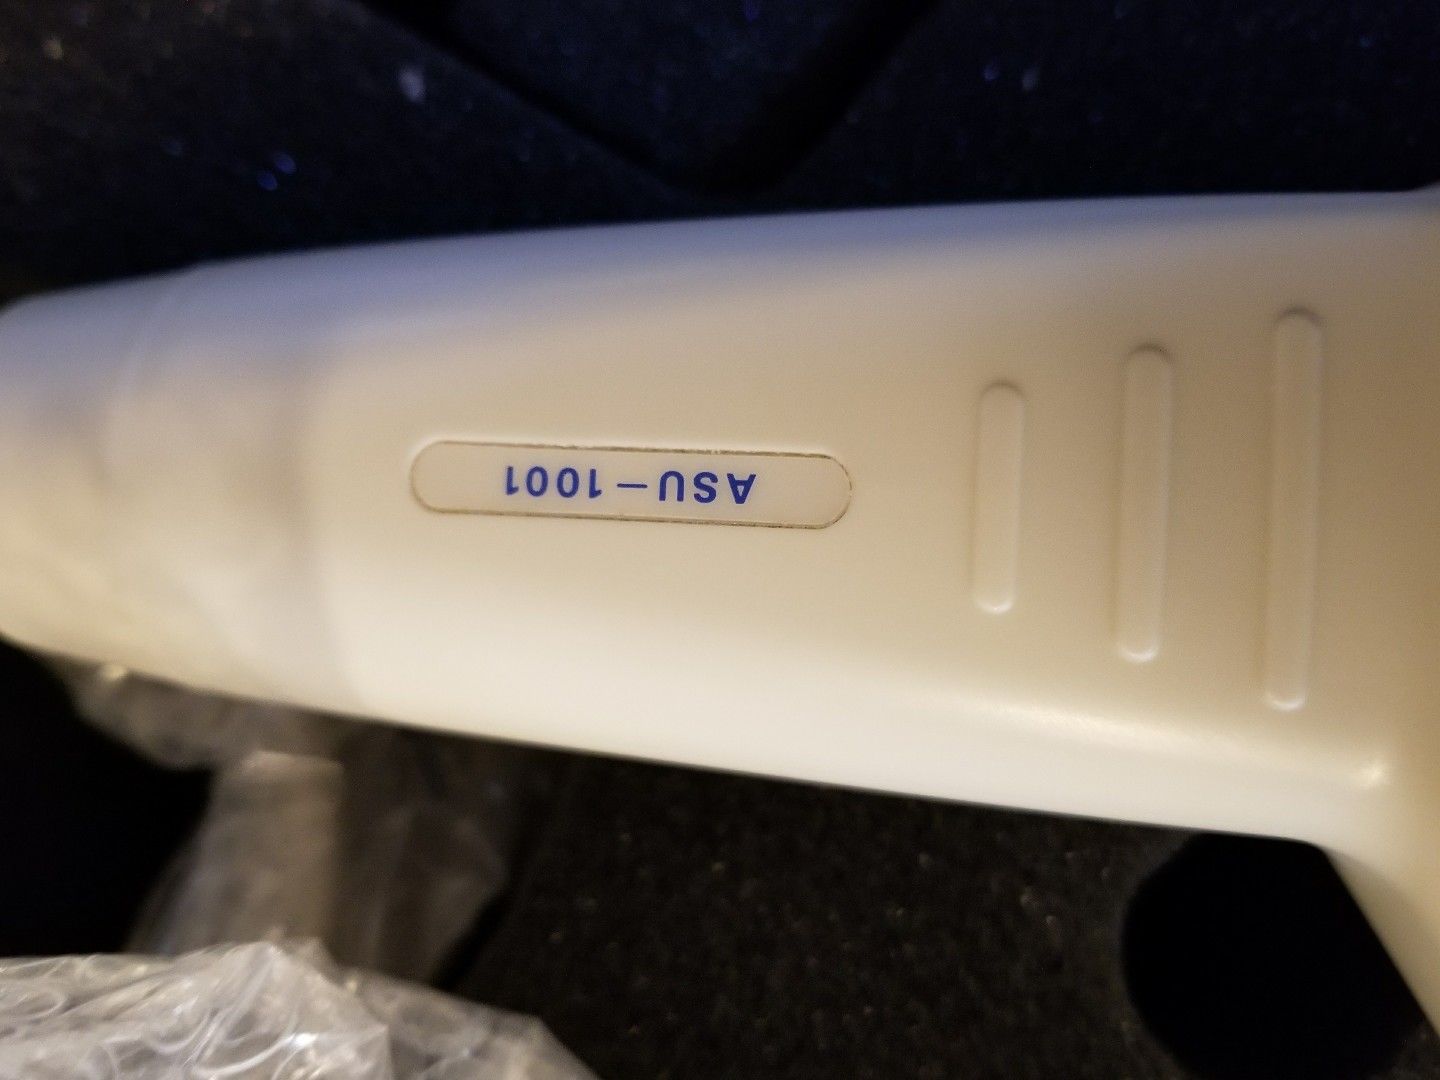

DIAGNOSTIC ULTRASOUND MACHINES FOR SALE

Aloka 620 DIAGNOSTIC ULTRASOUND SYSTEM W/ PROBES

Sale price$ 3,358.70